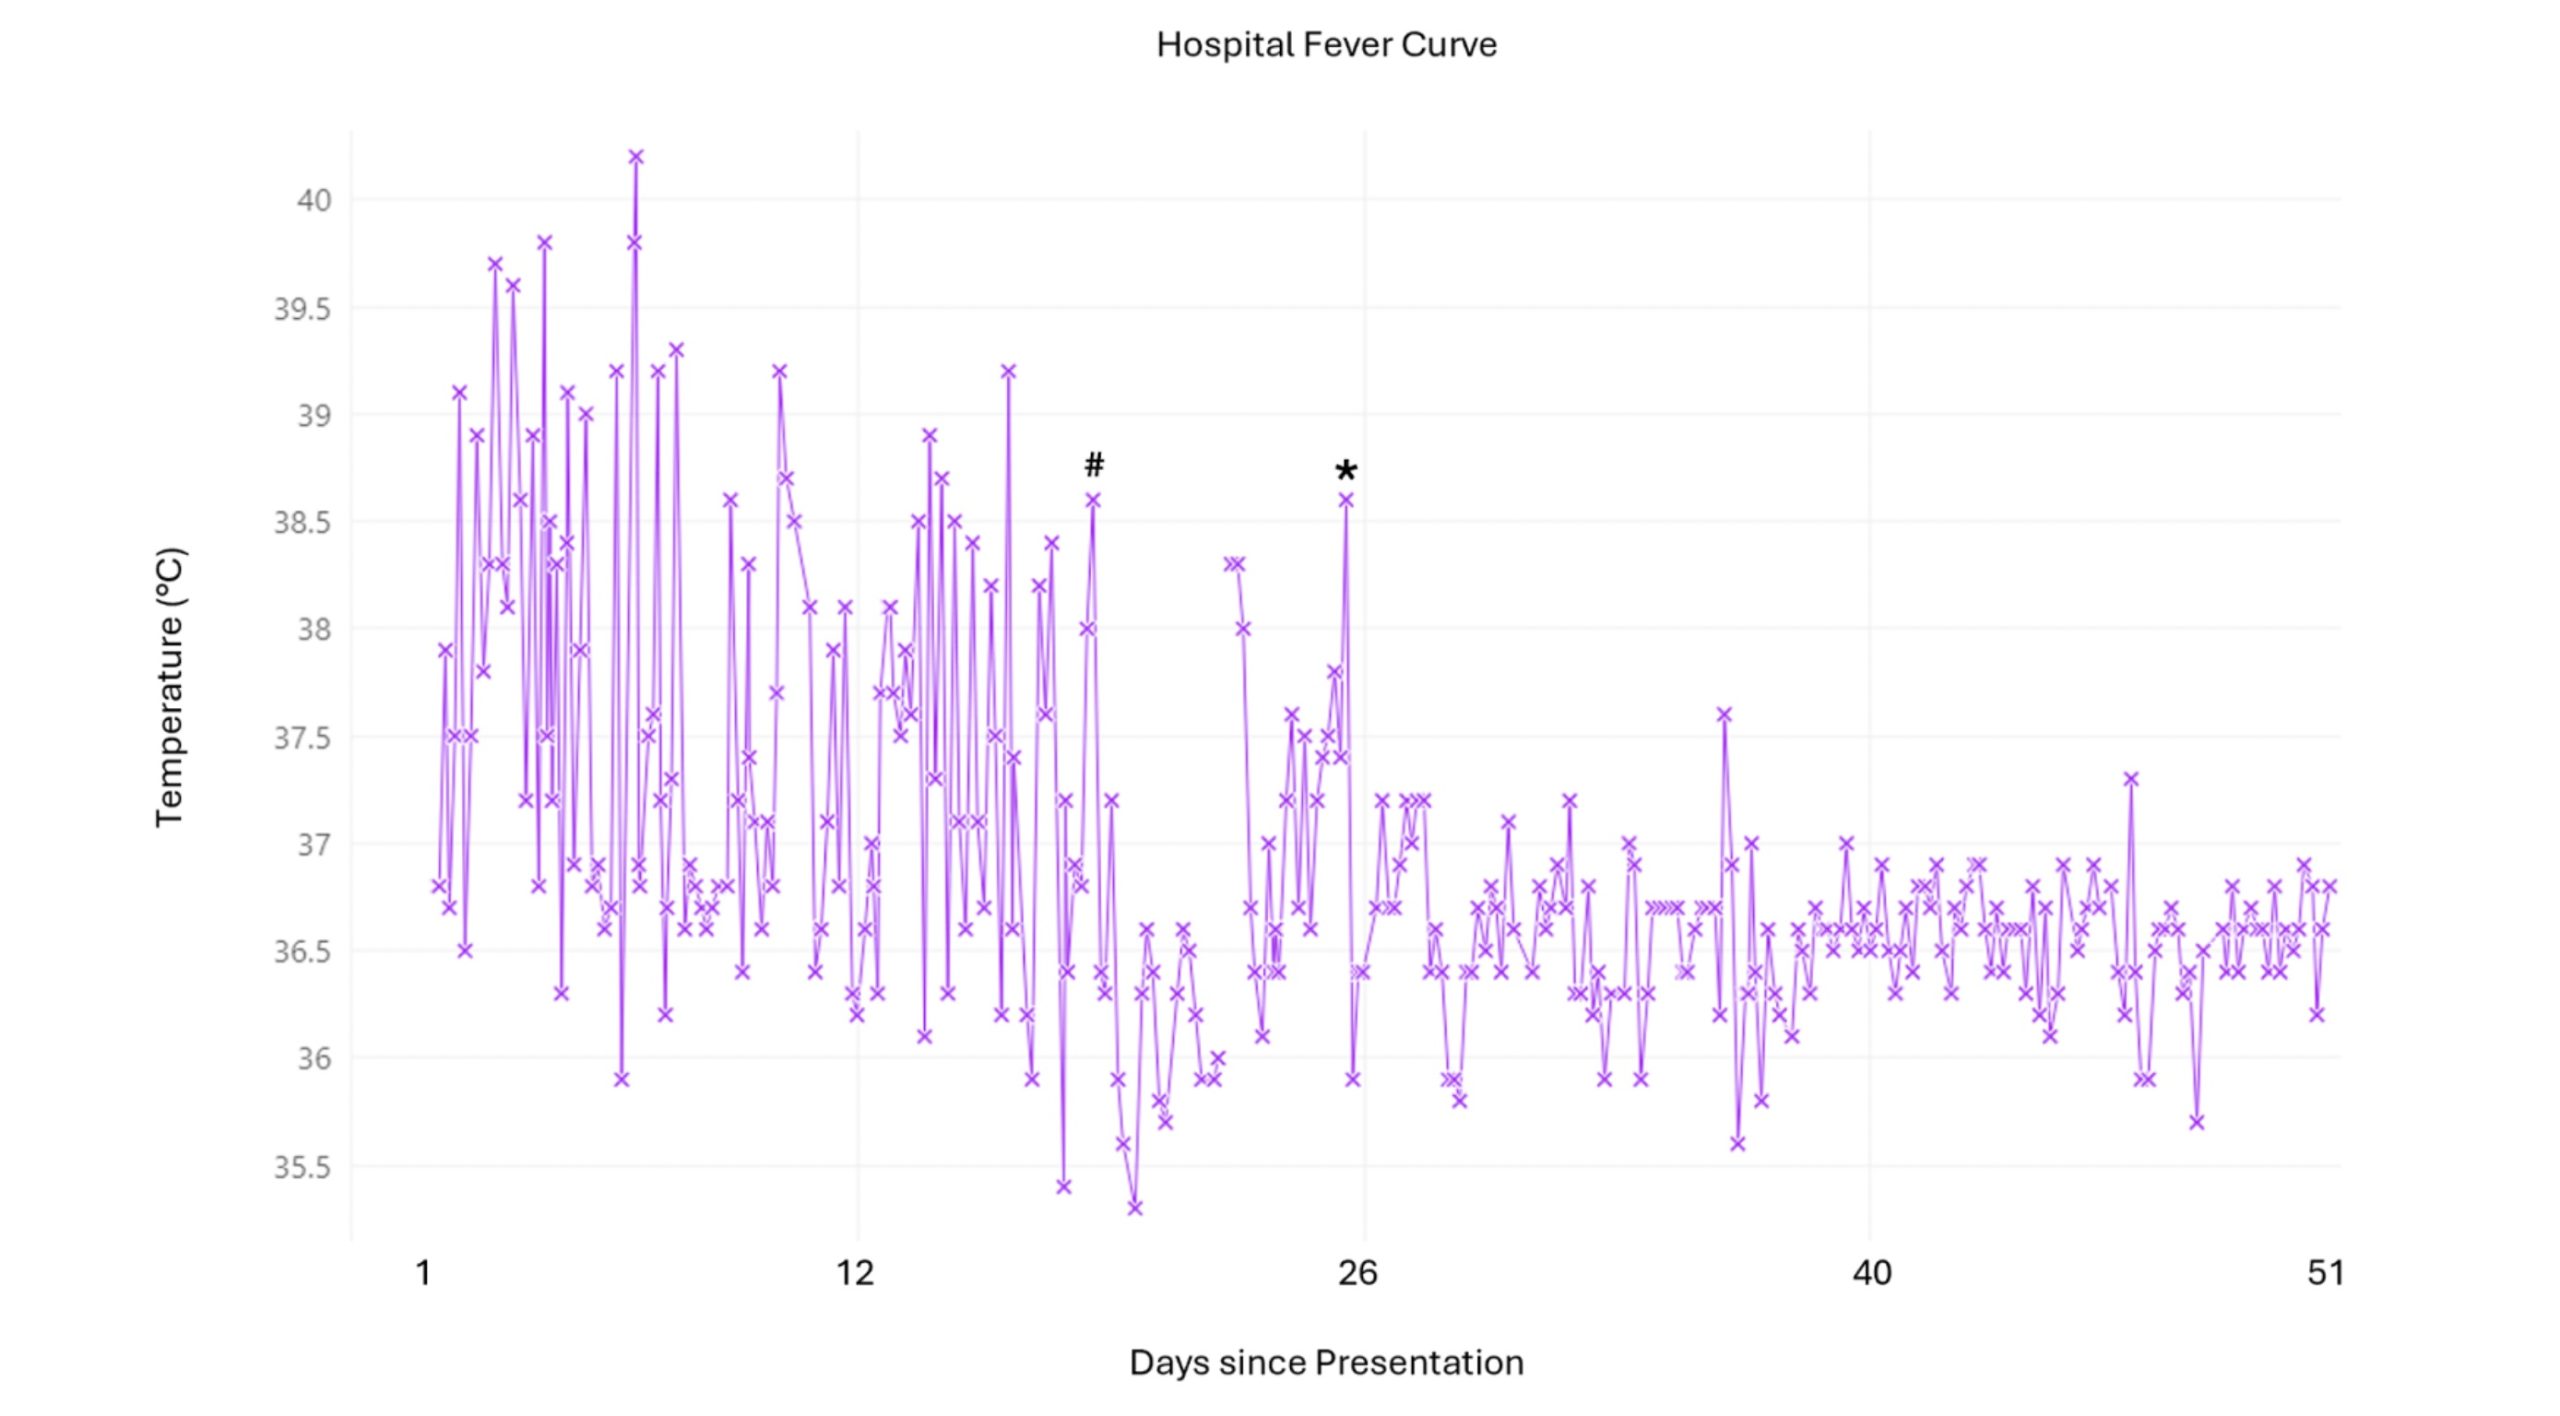

Case Presentation: We present a case of secondary Hemophagocytic Lymphohistiocytosis (HLH) triggered by Epstein-Barr Virus (EBV) in a 49 old male with no significant past medical history who worked as a cruise ship crewmember, presenting with high grade fevers and night sweats. Given his occupation, a broad differential diagnosis was initially considered, complicating timely diagnosis. From the initial testing, the patient was only positive for EBV IgG at a low titer. The patient continued with high fevers and developed acute liver failure which was treated with high dose steroids. Subsequent lymph node and bone marrow biopsies were negative. The patient then underwent a liver biopsy which demonstrated hemophagocytosis. HLH was eventually confirmed with other supporting laboratory tests. Fortunately, this patient survived after initiation of rituximab with dexamethasone.

Discussion: HLH is a rare but life-threatening autoimmune disease characterized by hyperinflammation and uncontrolled immune activation. The diagnosis of HLH in this patient was challenging due to his many non-specific symptoms, his occupation and the acute need for steroid use for his liver failure. This high dose steroid complicated diagnosis until a liver biopsy was performed demonstrating hemophagocytosis. It is important to note that hemophagocytosis can be seen in the spleen, liver or lymph nodes. Therefore a bone marrow biopsy, while helpful, is not crucial to the diagnosis and should not delay high dose steroid treatment for acutely ill patients. Additionally, a negative lymph node biopsy does not exclude diagnosis and clinical suspicion should prompt further investigation. Hemophagocytosis is neither pathognomonic, nor required for the diagnosis of HLH. In our case, other diagnostic criteria such as NK cell activity or CXCL9 were unavailable at our institution and so the presence of hemophagocytosis on liver biopsy was crucial in guiding diagnosis. Finally, HLH secondary to EBV specifically should be treated with rituximab. This is because EBV induces B lymphocyte proliferation while rituximab depletes B cells leading to improved outcomes for these patients.